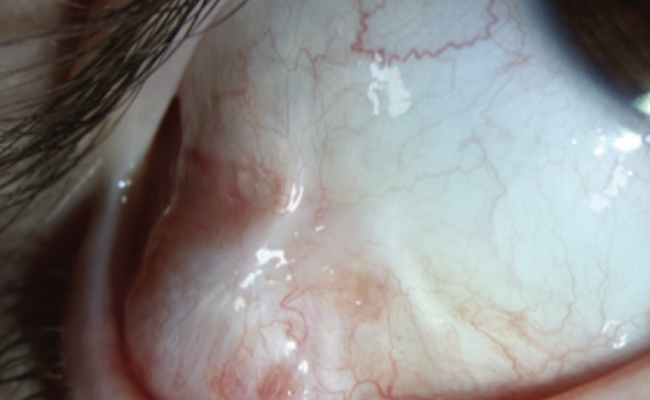

On examination, there was a solitary, 4-mm, well-defined, dome-shaped nodule with a bluish hue on the inferior border of the right temporal conjunctiva. There was no involvement of surrounding structures, including the eyelid margin (Figure 1). The lesion was excised, and the resulting defect was repaired by means of an amniotic membrane transplantation graft.